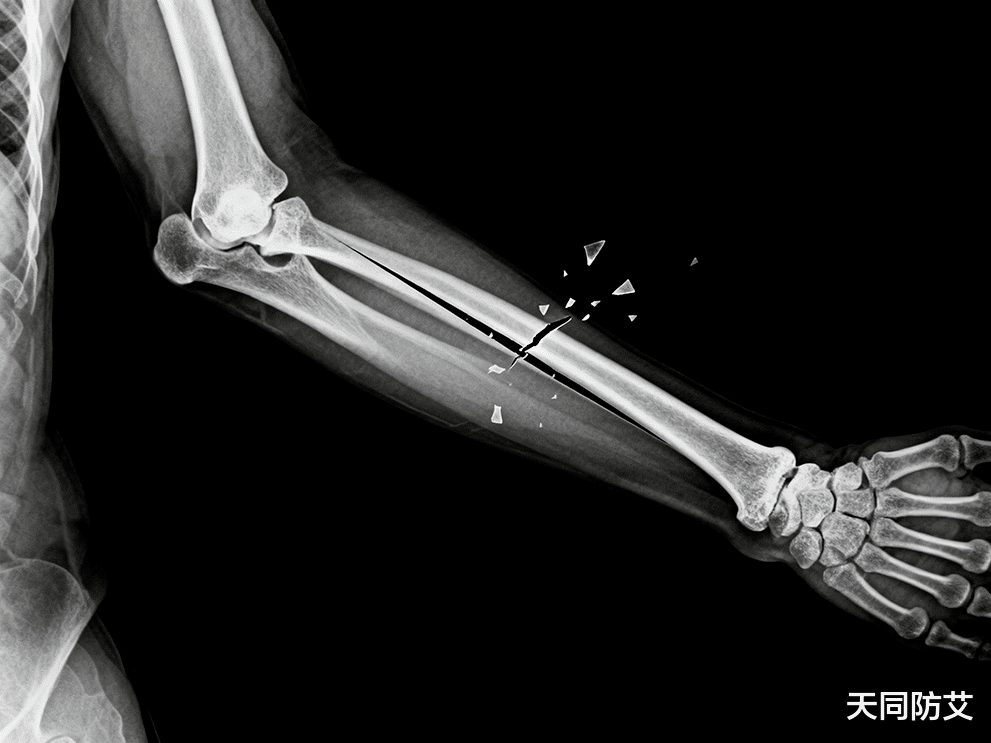

HIV感染会严重影响儿童的生长发育,常导致生长迟缓、青春期延迟、肌肉量减少和骨密度下降,从而增加骨折风险。青少年时期是骨骼构建的关键窗口期,此时获得的骨量峰值,将影响一生的骨骼健康。

这是一项严谨的随机、双盲、安慰剂对照试验,为期48周。研究人员使用双能X射线吸收法精确测量参与者脊柱骨密度的变化。